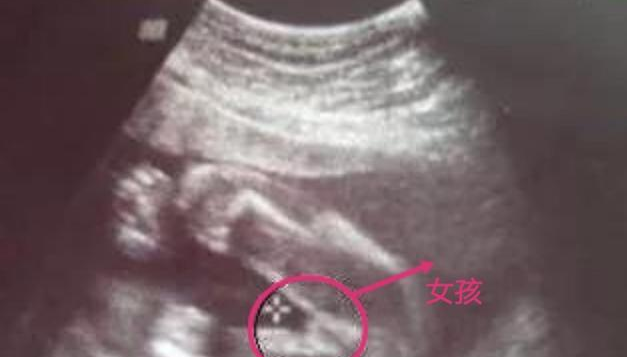

About Press Copyright Contact us Creators Advertise Developers Terms Privacy Policy & Safety How works Test new features Press Copyright Contact us Creators 超音波確認寶寶的性別 回到比較科學的確認,我第一次知道寶寶的性別是在 12 週,去照初唐篩檢時醫生暗示的,醫院好像不能明說寶寶是男生還是女生,只有照寶寶的胯下跟我說這裡沒有凸的形狀,就是暗示寶寶是女生啦~超 音 波 原 理 介 紹 一、何謂超音波: 1、普通人耳可聽到的聲音,頻率由16Hz 到 KHz,超音波以頻率高到人 耳聽不到的音波來定義。 2、超音波可以在空氣中,液體或固體中振動傳送。 3、超音波為依彈性(應變)發生的波動,一般不以人耳來聽為目的之音波。 4、一般區分為破壞性超音波與非破壞性超音波。 二、超音波的特徵: 超音波本質上與普通之音波並無什麼

→ cupcook 因為兩次超音波性別結果不同 所以我直接請醫生幫我 01/ 1530 → cupcook 確認當時NINFTY的資料 避免又被翻盤>"< 01/ 1530 推 chinimader 10w醫生說是男生,隔了一週說可能是臍帶在兩腿間目 04/30 1554 因此用超音波來看性別,並不是和大寶寶或是新生兒一樣直接看外型,而是看其「性突起」和身體長軸 (脊椎) 所夾的角度。 這個「性突起」就是將來男性要發育成龜頭、而女性要發育成陰蒂的構造,它和身體所夾的角度越大,是男性的機率就越高。用於量度距離。 通過超音波發射裝置發出超音波,根據接收器接到超音波的時間差就可以知道距離,與雷達測距原理相似。 超音波發射器向某一方向發射超音波,在發射的同時開始計時,超音波在空氣中傳播,途中碰到障礙物就立即返回來,超音波接收器收到反射波就立即停止計時。 (超音波在空氣中的傳播速度為v=340m/s,根據計時器記錄的時間t,就可以計算出發射點

超音波看胎兒性別的真相 王培中 Kingnet國家網路醫藥 Second Opinion

超音波看胎兒性別的真相